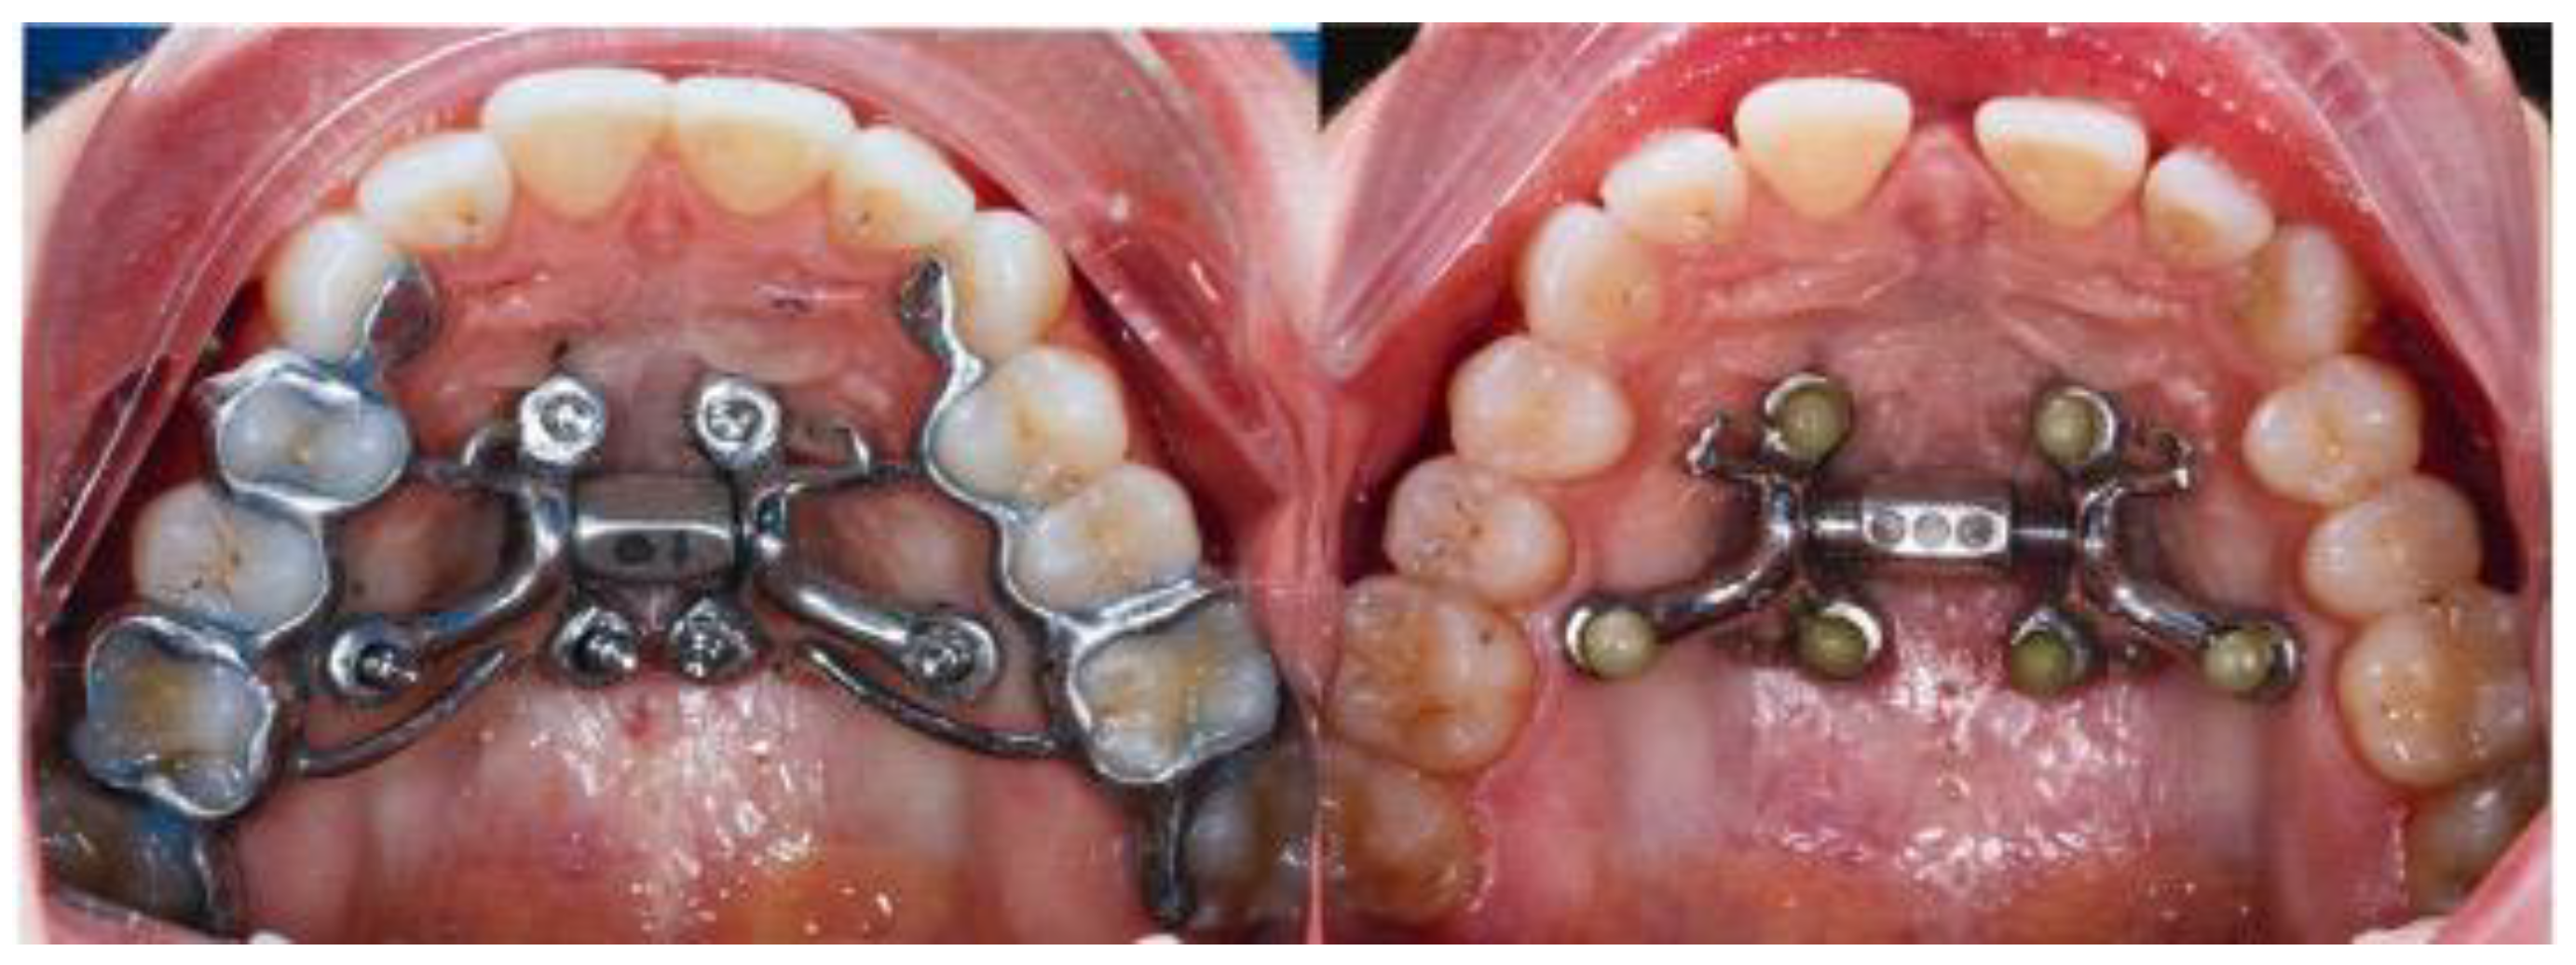

2.1. Description of MARPE Installation Procedure

2.5. Case B: Guide-Assisted Midpalatal Piezocorticotomy

2.6. Case C: Bilateral Posterior Crossbite with Guide-Assisted Expansion

2.7. Case D: Midfacial Asymmetry Correction with Guided Expansion